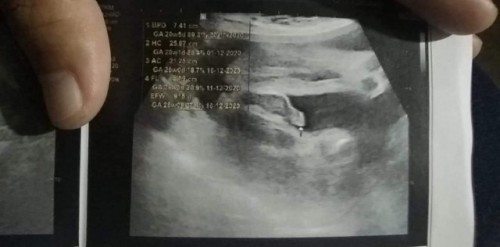

26w ของแม่ๆเพศไหนกันบ้างค่ะ

น้องไม่อายป้าหมอเลยค่ะ

บ้านนี้ยังไม่รุ้เพศลุกเลยคร่า 26 วิค 6 วันแล้วคร่า

อยากให้น้องอ้าเเบบนี้บ้างคะ😂บ้านนี้ไม่อ้าเลย